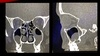

5